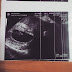

Llegamos y, como siempre, fue un enredo. Cuando vas por primera vez a un hospital que nunca has pisado todo es confuso y más confuso cuando es un hospital materno y una es primeriza. Una señorita muy amable pidió que me hiciera una ecografía, ¿acaso te vería por primera vez? ¿te escucharía por primera vez? ¿estarás bien? estas y muchas preguntas se apoderaron de mi mente. Papá se había quedado haciendo el papeleo para que pudieran atendernos (él es todo un capo en estas cosas y sabe hablar muy bonito) hasta que llegó el momento.

Luego que el doctor te busque pude verde en un rincón de mi ser, había algo que se movía de forma muy rápida, yo sabía que era tu corazón pero no esperé a que me lo dijeran y pregunté, insistente. El doctor me dijo que esperara, que en un segundo ya iba a escucharte, y así fue. Te escuché por unos segundos, latiendo fuerte, fuerte como un tamborcito y sí, lloré. Lloré mucho, pero esta vez fue de total alegría.

Ahí estabas pequeño, apareciste por fin en forma de arroz.